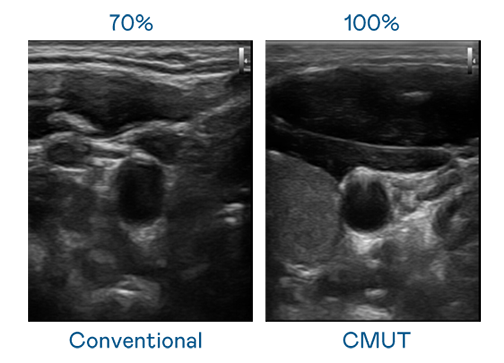

CMUT 技术是一种用电容式微机电元件来产生超音波讯号的技术。与传统 PZT 压电式技术相比,CMUT 频宽增加 30%,更宽频的超音波讯号让影像解析度大幅提升,是实现高影像品质医疗超音波扫描、促进精准医疗发展的关键技术。

超音波影像的解析度高低,首先取决于探头能发出的讯号频宽。stake CMUT 可提供高清晰的超音波讯号,提供高频宽、高灵敏度、影像纹理细节更高的超音波影像,协助医护人员缩短影像判读时间及利用精准的医疗影像进行诊断。